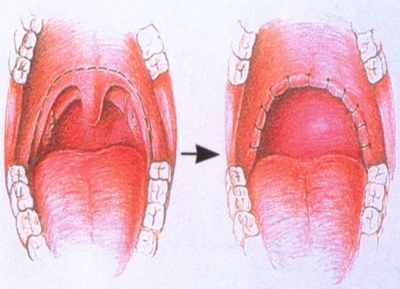

人は通常上気道を広げる筋肉が緊張していて、気道を広げて、呼吸している。眠りが深くなるとこの緊張が解けて、気道が狭くなるとともに、舌の根元がのど側に下がって食道と気道とを切り替えている軟口蓋を塞ぎ、気道が狭くなり、いびきが生じ、これがはなはだしい場合、気道が閉じて無呼吸となる。